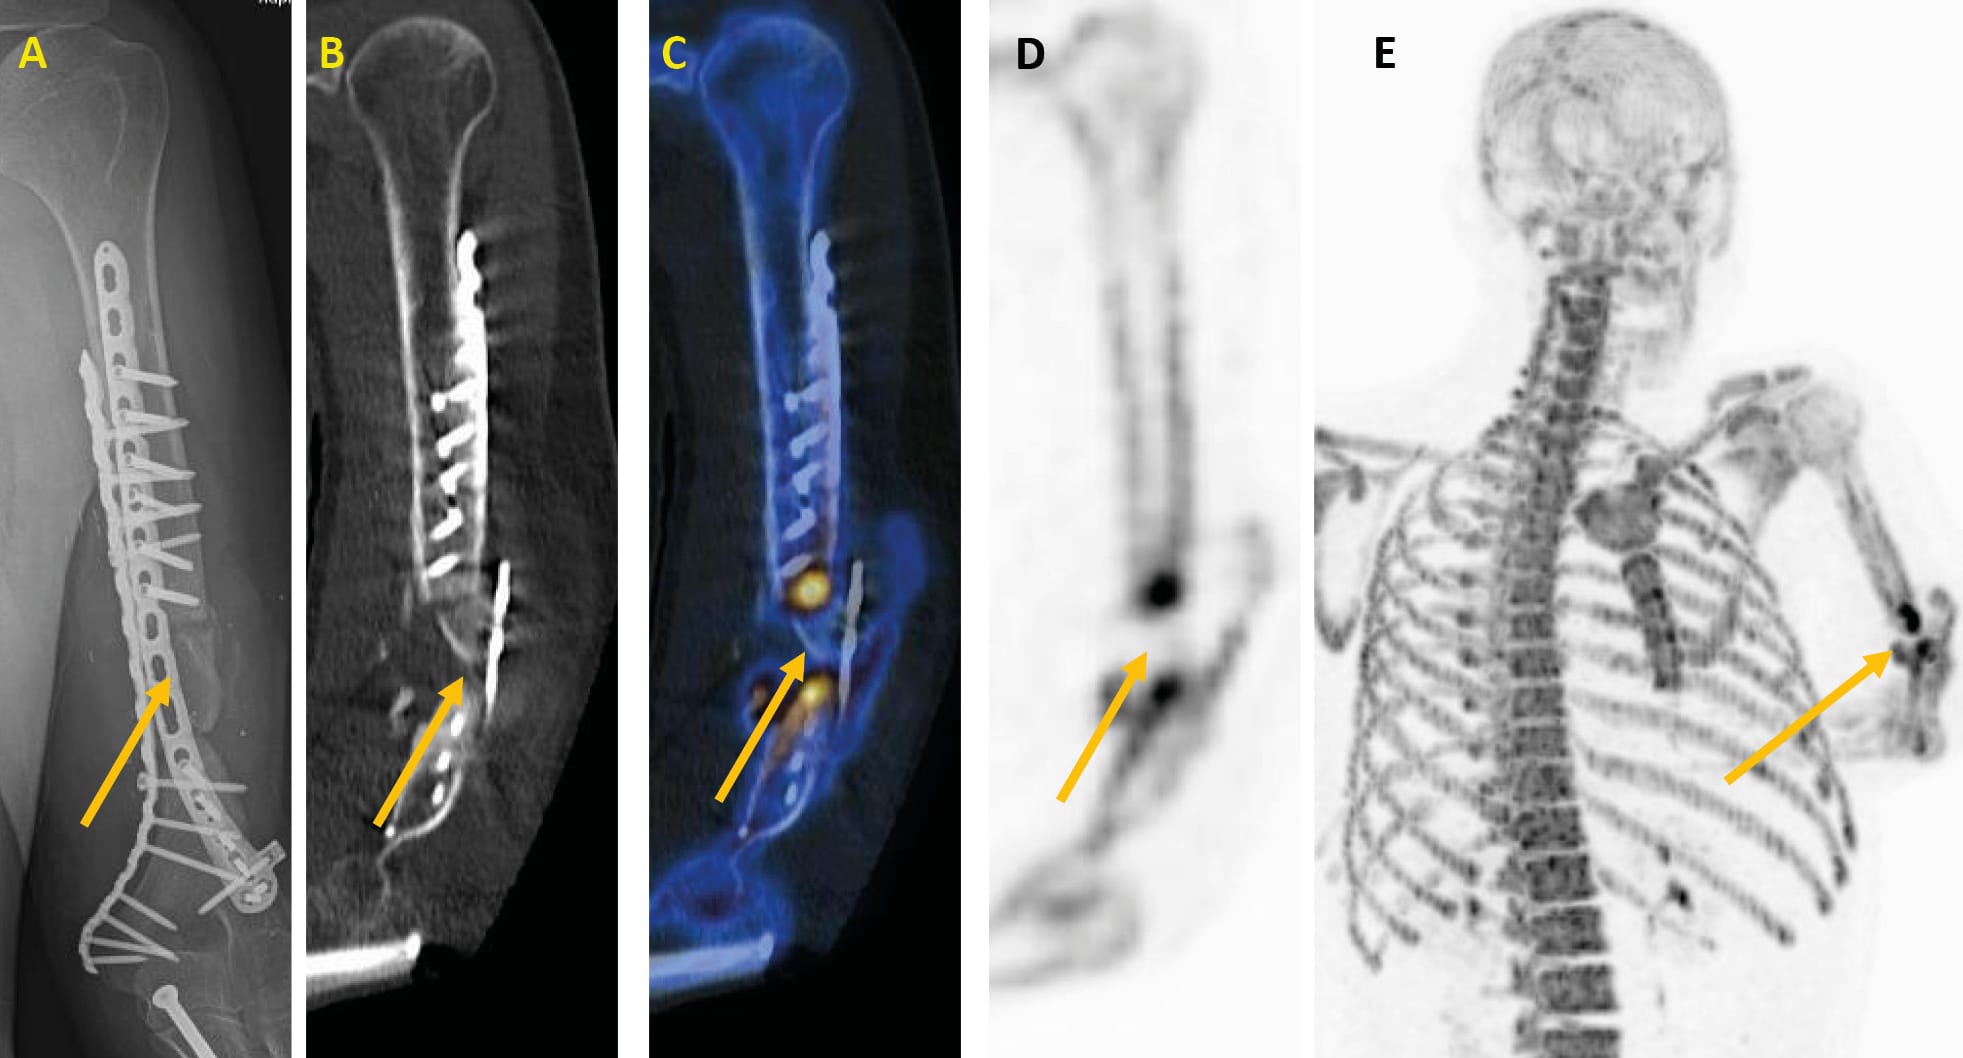

Figure 4 has a radiograph with a vascularised bone chip on the left humeral shaft on the left side, which shows no healing tendency months after reconstruction. On the right side of figure 4 the result using Na[18F]F-PET/CT. It can be clearly seen that the vascularised chip no longer has a bone metabolism. The chip is avital and must be removed. Cancelliosaplasty cannot be successful in this case.

In most cases, the patients had multiple injuries. In many cases there were chronic wounds and older fractures. Anti-granulocyte antibody (AGA) scintigraphy and SPECT/CT examinations were used in these cases in order to be able to reliably distinguish between Post-traumatic osteomyelitis (PTO), also known as ‘fracture-related’ osteomyelitis with increased AGA uptake and non-specfic changes in the case of ambiguous wound conditions. For treatment planning, it was also important to know which fragments of the fractures were avital in order to remove them and thus eliminate a possible reservoir for bacteria. For this purpose, we used 18F sodium fluoride (Na[18F]F) PET/CT examinations to detect avital bone fragments.

18F sodium fluoride (Na[18F]F) is a positron emitter and is used as a radiopharmaceutical in PET/CT. It has a similar pharmacokinetic behavior to the 99mTc diphosphonates used in gamma camera skeletal scintigraphy (SPECT). However, Na[18F]F-PET/CT has the advantage of a higher spatial resolution and specificity compared to skeletal scintigraphy. As a dynamic examination, Na[18F]F-PET is mainly used clinically in the vitality diagnostics of bone grafts. A reduced fluoride influx in the perfusion phase indicates that the graft is no longer vital [18] Wong KK, Piert M (2013) Dynamic bone imaging with 99mTc-labeled diphosphonates and 18F-NaF: mechanisms and applications. J Nucl Med 54:590-599. The dynamic examination approach in PET/CT is currently not widely used because it requires the drug to be produced in a PET radiopharmacy according to GMP (good manufacturing practice) guidelines.

The dynamic Na[18F]F-PET/CT established at the German Armed Forces Hospital Ulm is excellently suited for vitality diagnostics of delayed-unions or non-unions and forms a basis for further treatment planning or redirection. The advantages of this tracer with unsurpassed image quality, shorter examination time and the possibility of dynamic examination including quantification are thus available for complex traumatological issues.